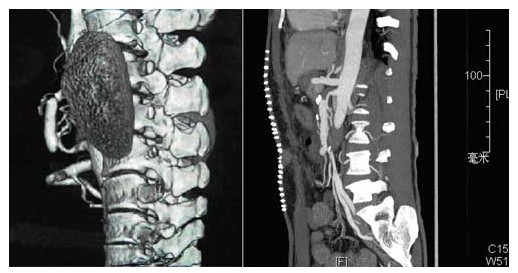

由于Hirooka分型过于繁杂,不便实用。汪忠镐综合各种分类方法,根据下腔静脉阻塞的特性、肝静脉受累的情况,从便于手术选择的角度将本病分为3种类型(图1)。

Ⅰ型:下腔静脉隔膜为主的局限性狭窄或阻塞型(约占57%)。此型系高位下腔静脉隔膜样阻塞或纤维性阻塞,肝静脉未被累及,但是,肝静脉开口位于下腔静脉阻塞的远侧。因此,除下腔静脉有阻塞外,肝静脉回流亦受阻。此型在日本相当多见。下腔静脉阻塞的远侧,血流淤滞,可继发血栓形成。若血栓延伸,即可堵塞肝静脉开口和主干。

Ⅱ型:弥漫性狭窄或阻塞型(约占38%)。下腔静脉弥漫性狭窄或阻塞,肝后段下腔静脉节段性或弥漫性阻塞,合并左肝静脉或右肝静脉闭塞,甚至肝静脉主干全部闭塞。亚洲和远东地区所见者多属此型。

Ⅲ型:肝静脉阻塞型(约占5%)。肝静脉主干或开口阻塞,下腔静脉通畅。此型多发生在西欧和北美地区。常表现为肝静脉血栓形成或血栓性静脉炎。有学者观察到,随着病程的延长,肝静脉出口附近的下腔静脉继发血栓形成。